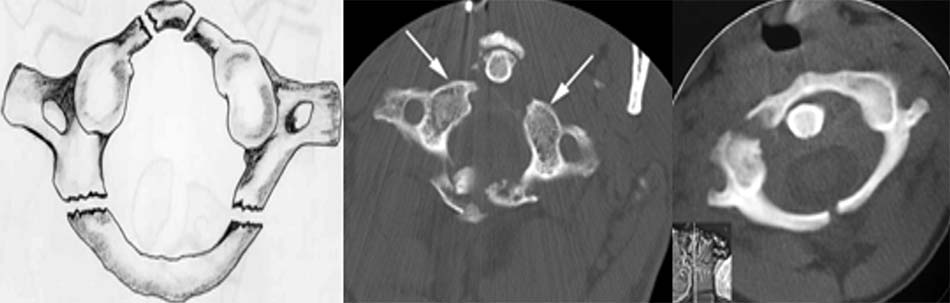

2.1.5. Gãy C2 (gãy Hangman)

Gãy Hangman được Wood – Jones mô tả đầu tiên vào năm 1913 ở những nạn nhân bị kết án treo cổ. Theo một số nghiên cứu, gãy Hangman chiếm tỉ lệ 12-18% trên tổng số gãy cột sống cổ, 25 – 40% trong số này chết sau tai nạn, số còn lại chỉ có từ 3 – 10% có tổn thương thần kinh.

Gãy Hangman là sự phối hợp của cơ chế ưỡn quá mức và dồn ép chủ yếu do tai nạn giao thông, đường gãy qua 2 chân cuống với giật đứt C2. Khi cơ chế ưỡn chiếm ưu thế, dây chằng dọc trước bị rách kèm đứt kèm theo đứt mảnh xương nhỏ ở vành ngoài của C2 hoặc C3. Khi ưỡn nhiều hơn làm rách cả đĩa đệm và dây chằng dọc sau làm thân C2 trật ra trước gây mất vững. Tuy nhiên cung sau C2 vẫn ở nguyên vị trí vì chân cuống bị gãy hai bên, ống tuỷ được mở rộng ra và không gây thương tổn tuỷ [38],[42].

Có nhiều cách phân loại gãy Hangman, thông dụng nhất là phân loại của Effendi và cộng sự, sau này được Levine và Edwards thay đổi [37].

- Loại I: Gãy ngang qua diện khớp hai bên hoặc ở đoạn trên hay dưới diện khớp, di lệch dưới 3mm, không gập góc. Loại này hay phối hợp các thương tổn khác như gãy cung sau C1, gãy Jefferson, gãy mỏm nha.

- Loại II: Di lệch trên 3mm, gập góc tì lên góc trên trước C3.

- Loại IIA: Gập góc nhưng không di lệch hoặc lệch không đáng kể. Trong loại này dây chằng dọc sau và đĩa đệm rách.

- Loại III: Di lệch và gập góc nhiều, kèm trật khớp C2-C3 một hay hai bên. Dây chằng dọc trước và sau rách hoàn toàn.